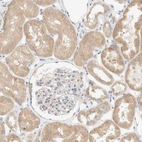

Immunohistochemical staining of human intestine shows strong cytoplasmic positivity in glandular cells.